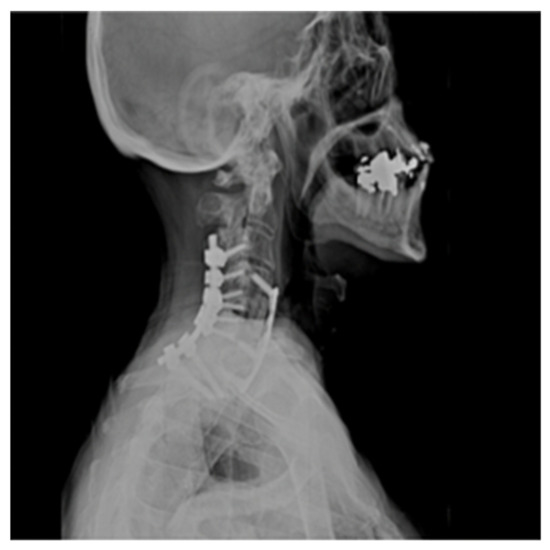

3.1.5. Case Illustration 1

The patient was admitted to the intensive care unit and Mean Arterial Pressures (MAPs) were maintained at 90 mmHg, and he was fully anticoagulated with a heparin drip. He, however, developed significant airway edema and respiratory distress within 24 h after anticoagulation and hypertensive therapy. The patient thus required emergent intubation and subsequent operative hematoma evacuation. Lateral radiograph 1-year post operation shows C4–C7 fusion hardware and resolution of hemodynamic instability (Figure 4).

Figure 4. Lateral Radiograph Post Op 1 Year.